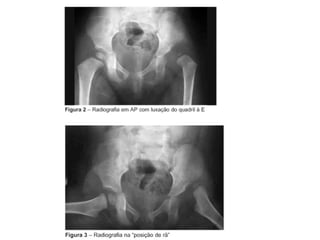

INCIDÊNCIAS PELVE

IDENTIFICAÇÃO DA RADIOGRAFIA

UNILATERAL

ESTRUTURAS MAIS DEMONSTRADAS: Cabeça, colo do fêmur e tocantes.

INCIDÊNCIAS QUADRIL